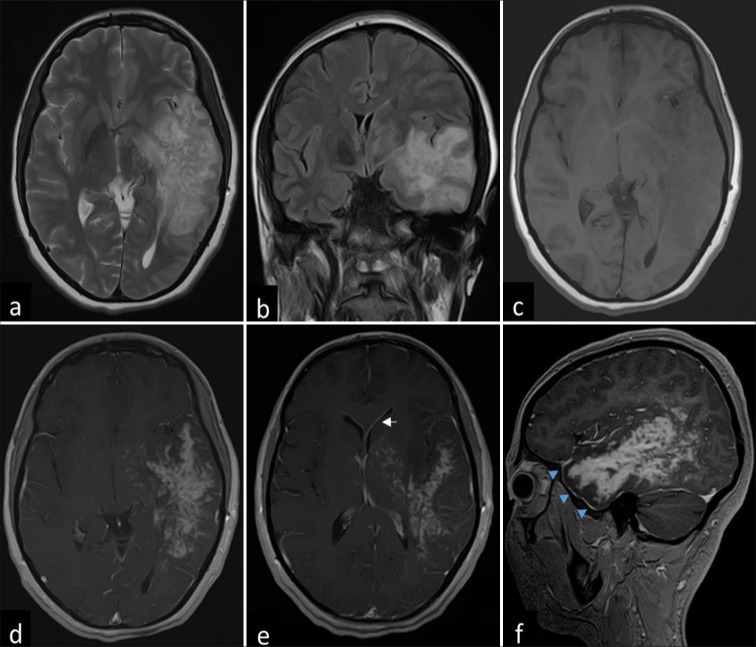

Case description: Herein, we report the presentation of a 34-year-old immunocompetent Pashtun female with acute-onset rapidly progressing generalized weakness, altered cognition, and motor and speech deficits. Although the radiological findings resembled a glioblastoma, the strong clinical suspicion of a fungal infection and her improvement on voriconazole treatment led to the decision to avoid surgical resection, thereby minimizing the risk of potential dissemination.